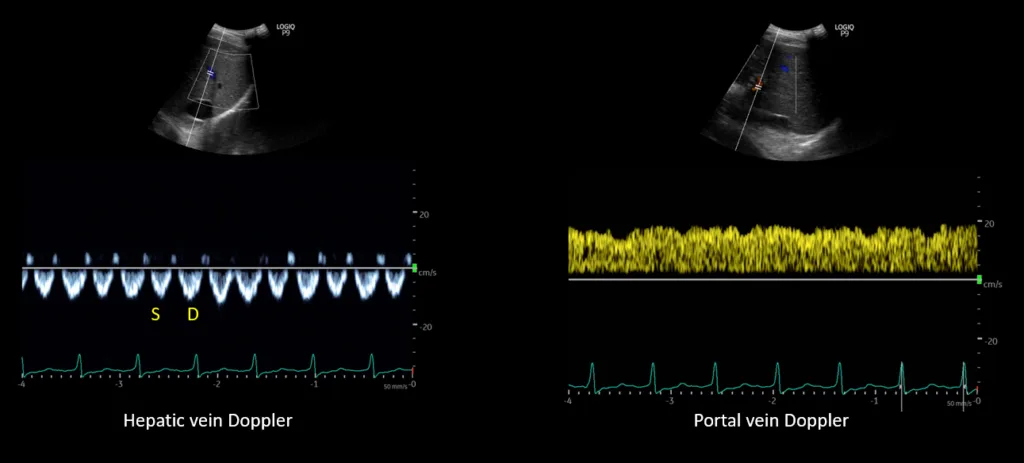

A 53 year old man with heart failure with reduced ejection fraction (~37%) secondary to non-ischemic cardiomyopathy and end-stage kidney disease (ESKD) recently initiated on hemodialysis underwent a right upper quadrant ultrasound for elevated liver function tests. Despite a radiology report indicating “normal liver morphology and hemodynamics,” a review of images by the nephrology team revealed severe venous congestion. This was evidenced by a dilated inferior vena cava (IVC) with an approximate anteroposterior diameter of 3 cm, systolic (S-wave) reversal in the hepatic vein flow, and a pulsatile portal vein with some flow reversal (Figure 1). These sonographic findings are consistent with VExUS grade 3 (Figure 2).

Figure 2. Venous excess ultrasound grading: When the diameter of the inferior vena cava is > 2 cm, three grades of congestion are defined based on the severity of abnormalities on hepatic, portal, and renal parenchymal venous Doppler. Hepatic vein Doppler is considered mildly abnormal when the systolic (S) wave is smaller than the diastolic (D) wave, but still below the baseline; it is considered severely abnormal when the S-wave is reversed. Portal vein Doppler is considered mildly abnormal when the pulsatility is 30% to 50%, and severely abnormal when it is ≥ 50%. Asterisks represent points of pulsatility measurement. Renal parenchymal vein Doppler is mildly abnormal when it is pulsatile with distinct S and D components, and severely abnormal when it is monophasic with D-only pattern. Adapted from NephroPOCUS.com with permission.

Interestingly, the patient lacked pedal edema or shortness of breath. A formal echocardiogram demonstrated reduction of left ventricular ejection fraction from a baseline of 37% to ~30%, new right ventricular enlargement with interventricular septal flattening (D-sign), and severe functional tricuspid regurgitation, suggestive of fluid overload (Figure 3). The patient history was not suggestive of pulmonary embolism. A nuclear medicine stress test was negative for ischemic changes. Over the subsequent three days, the nephrology team performed daily ultrafiltration, resulting in removal of 8 liters of fluid (net negative 4.5 liters on day 3). At the end of the second session, the nephrology team performed a follow up VExUS scan that showed significant improvement in the congestion. The portal vein was completely normalized, whereas the hepatic vein showed mild congestion with S-wave less than D-wave. A simultaneous ECG tracing was used to avoid errors in misidentification of the waves (Figure 4).

Figure 4. POCUS images demonstrating S<D pattern on hepatic vein Doppler and a normal appearing (pulsatility <30%) portal vein waveform.